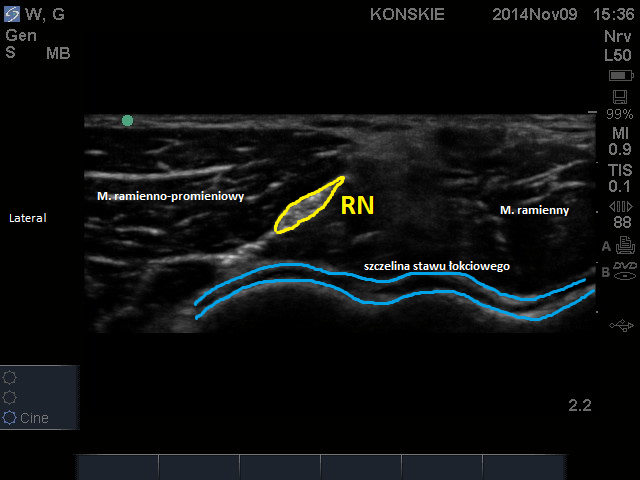

W obrazie ultrasonograficznym w okolicy jednej trzeciej dystalnej ramienia n. promieniowy przybiera kształt trójkątnego hiperechogenicznego tworu, położonego pomiędzy mięśniem trójgłowym a głową boczną mięśnia dwugłowego. W okolicy dołu łokciowego n. promieniowy początkowo biegnie w powięzi pomiędzy mięsniem ramienno-promieniowym a mięśniem ramiennym gdzie mniej więcej na wysokosci 2-3 cm powyżej bruzdy łokciowej, ukazuje się jako podłużna, wrzecionowata, hiperechogeniczna struktura, wciśnięta pomiędzy dwa wyżej wymienione mięśnie.

Sonoanatomia nerwu promieniowego na wysokości szczeliny stawu łokociowego. RN – nerw promieniowy (radial nerve)